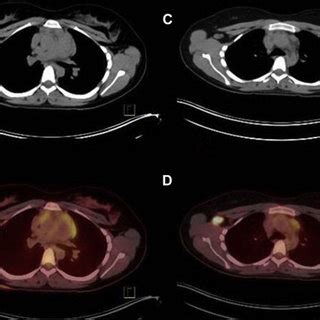

2-Deoxy-2- 18F Fluoro-D-Glucose : Fundamental Limitations of 18F2-Deoxy-2-Fluoro-d-Glucose ... / Fdg mimics glucose chemically and structurally.. Actual study start date : Willis1,2* and arif sheikh3 1department of pathology and laboratory medicine, university of north carolina, chapel hill, nc, usa 2mcallister. The positron emission tomography/computed tomography (pet/ct) scanner, in which pet and ct are combined. Retrospective pet study and animal experiment. There has been extensive research on the utility of pet for sclc in terms of improved staging, restaging.

Retrospective pet study and animal experiment. The positron emission tomography/computed tomography (pet/ct) scanner, in which pet and ct are combined. There has been extensive research on the utility of pet for sclc in terms of improved staging, restaging. Fludeoxyglucose f 18 injection (fdg) is provided as a ready to use isotonic, sterile, pyrogen free, clear, colorless citrate buffered solution. Actual study start date : Willis1,2* and arif sheikh3 1department of pathology and laboratory medicine, university of north carolina, chapel hill, nc, usa 2mcallister. Polyoma middle t antigen (pymt) and mouse mammary tumor. Fdg mimics glucose chemically and structurally.